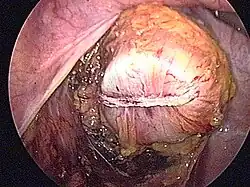

- Schematyczne obrazy jelita grubego i uchyłków esicy i śródoperacyjne obrazy uchyłków i nowotworu jelita grubego

Śródoperacyjny widok uchyłków esicy (operacja laparoskopowa).

Śródoperacyjny widok nowotworu esicy (operacja laparoskopowa).